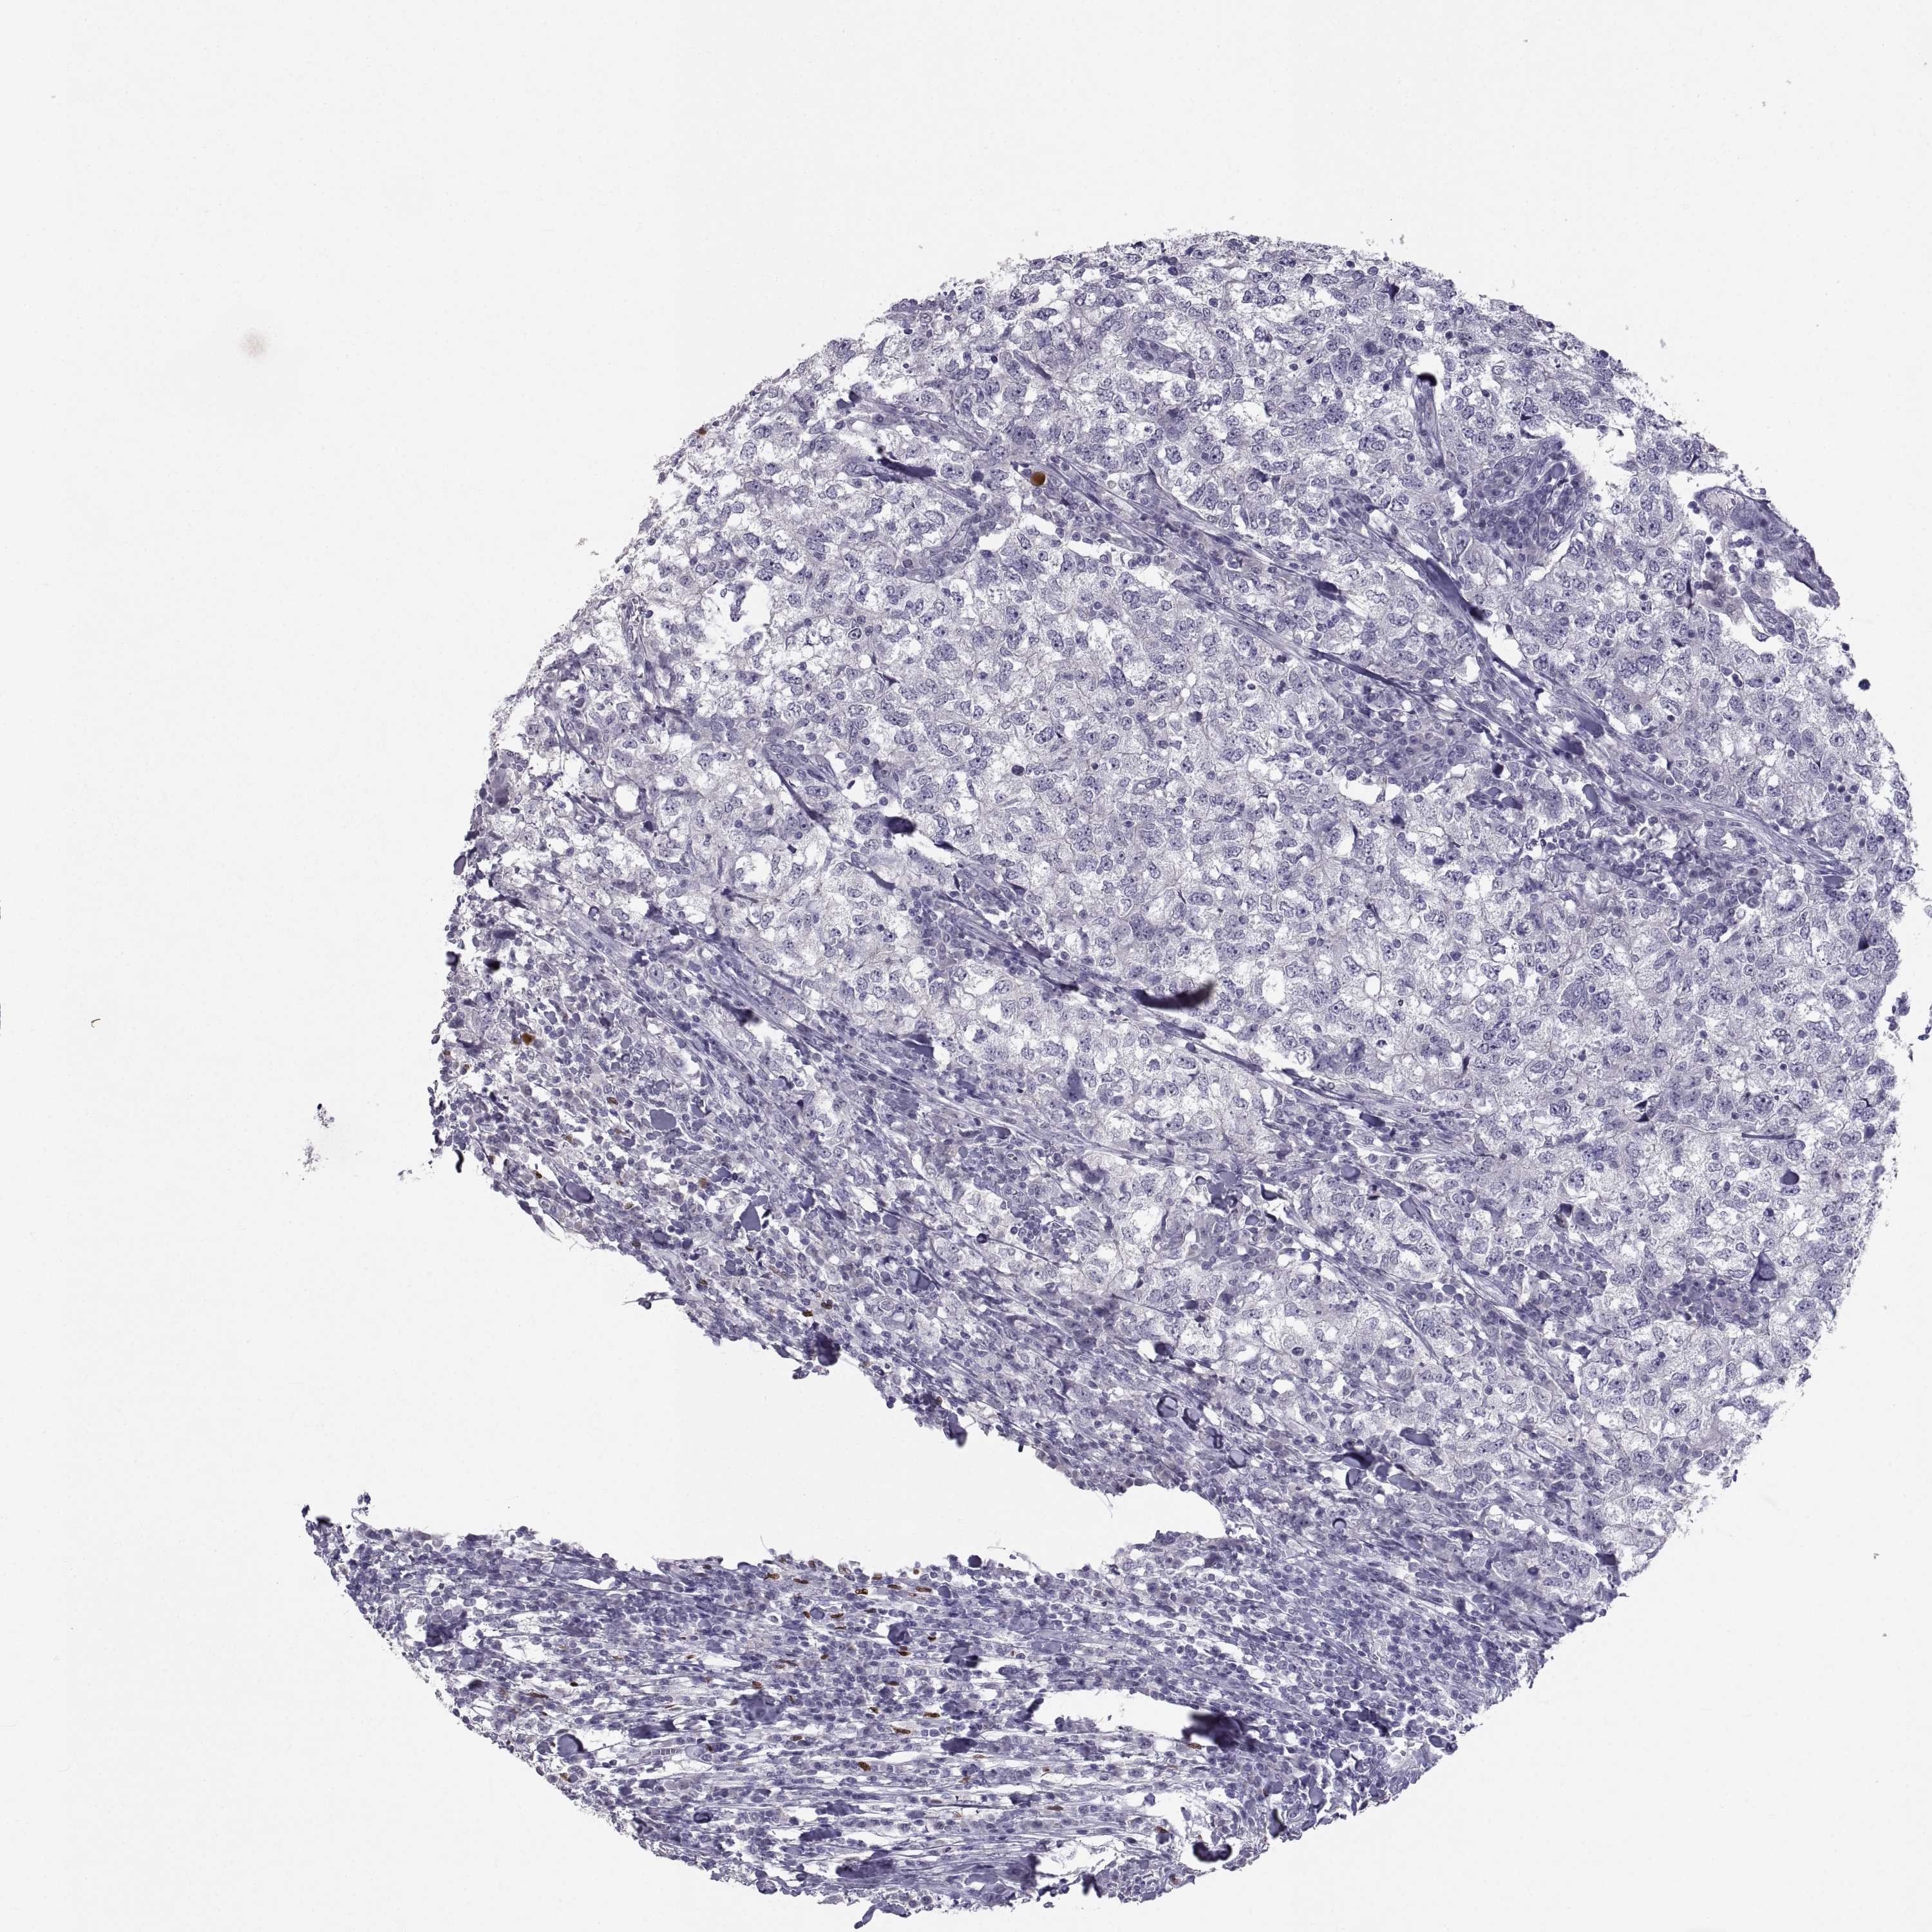

CANCER BREAST CANCER Show tissue menu

Breast cancer

Human cancer